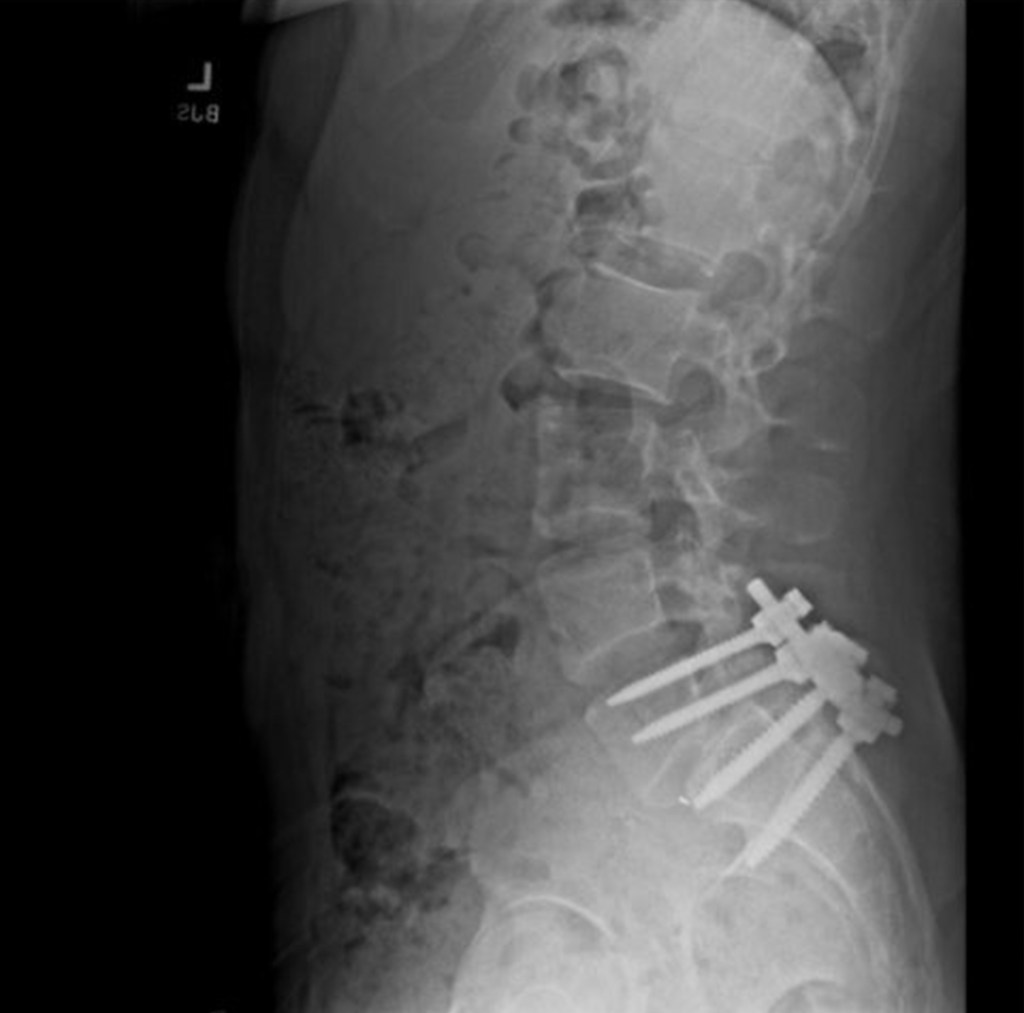

He used to be in a state of constant pain due to a pinched nerve and a misaligned spine, as reported by The New York Times.